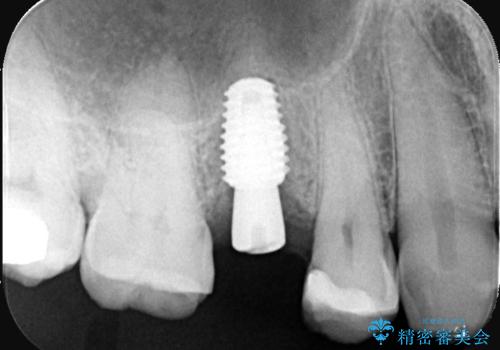

右上5番が根尖性歯周炎と歯周病が同時に併発しており、骨が大きく溶け、歯の動揺も著しかったため保存困難と判断をし抜歯してインプラントで治療を行いました。

インプラントはインプラント周囲炎になりにくいスクリュータイプを使用しています。

右上4番は虫歯になっていたので、虫歯を除去後、セラッミクインレーで治療を行いました。

- 税込814,000円(インプラント10年保障297,000円+カスタムアバットメント110,000円+オールセラミッククラウンエクセレント220,000円+骨造成55,000円+セラミックインレー77,000円act)費用は治療当時の料金となります

従来のインプラント治療では、オペを二回に分けることが主流でしたが今は1回のオペで治療を終える事が出来るようになりました。

インプラントと骨が強度にくっつくように骨密度を上げながらドリリングを行っているのと、患者様の骨の状態に合わせてインプラントの形態を選ぶことで可能となっています。

オペの回数を最小にする事で患者様の治療への負担が減り、治療期間も従来の治療より大幅に短くする事が可能です。